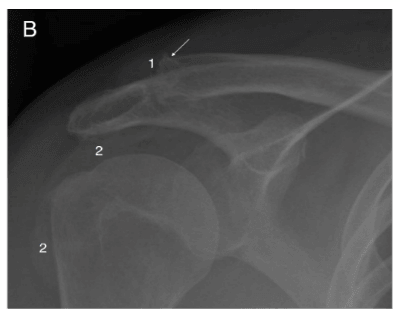

Gout In Shoulder

I never had an episode of gout before this one. Shoulder. Detected by MRI and my visit to an orthopedic surgeon. The episode was horribly painful. The reversal (cure) has been fairly swift.

My conservative physicians steered away from pharma Rx and instead directed me to exercise through the pain, eats lots of tart dried cherries, drink huge amounts of water. I have applied some NSAID Rx creme to the shoulder and the inflammation reduced.

I’m back to nearly full range of motion and normal amounts of pain (I am a golfer) in one week.